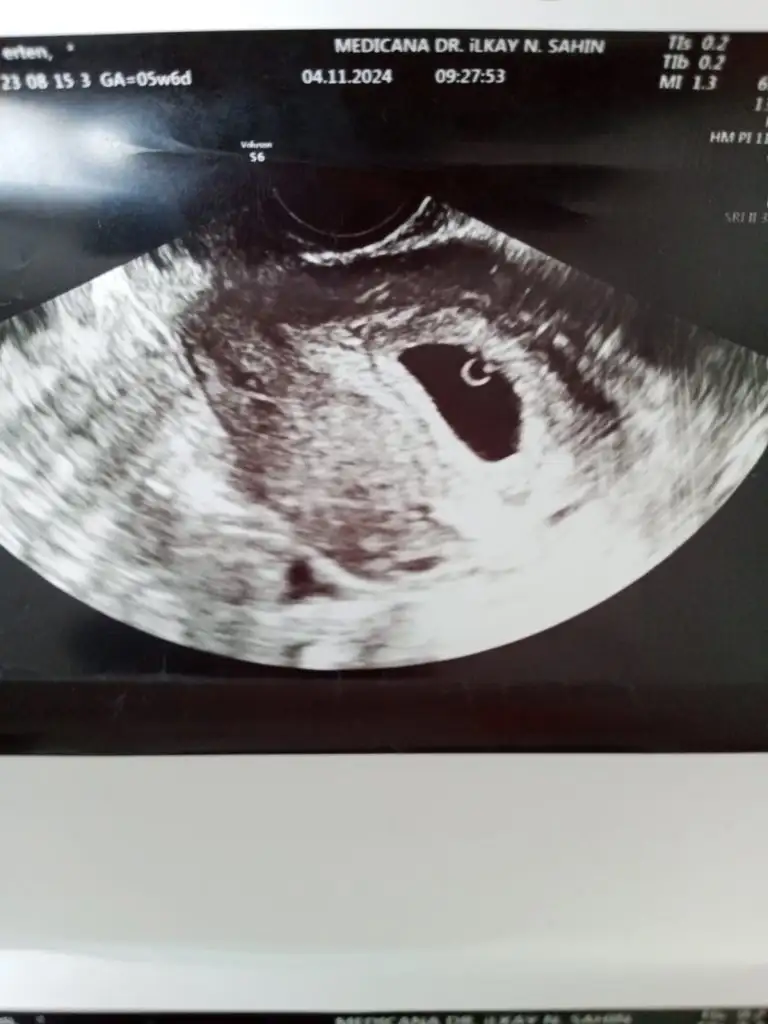

Bende tahmin alabilirmiyim

• IMG-20241114-WA0046.webp

IMG-20241114-WA0046.webp

21,4 KB · Görüntüleme: 63

• IMG-20241104-WA0021.webp

IMG-20241104-WA0021.webp

28,7 KB · Görüntüleme: 52

• IMG-20241104-WA0019.webp

IMG-20241104-WA0019.webp

26,1 KB · Görüntüleme: 48